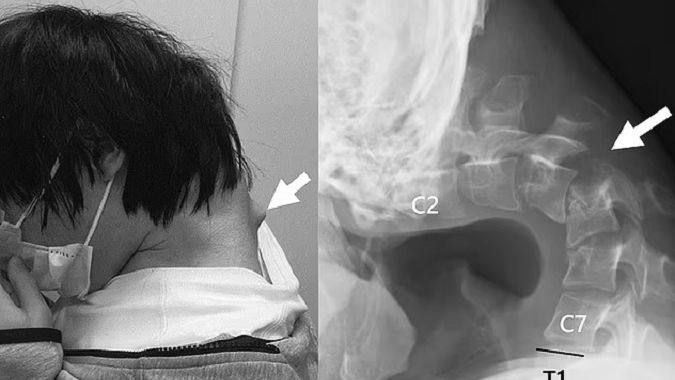

W kolejnych etapach zdecydowano się na interwencję chirurgiczną, która polegała na usunięciu uszkodzonych fragmentów kręgów oraz zbliznowaciałych tkanek. Następnie wstawiono do kręgosłupa metalowe pręty i śruby, które ustabilizowały szyję i umożliwiły powrót do prawidłowej postawy.

Efekty okazały się spektakularne. Po sześciu miesiącach od operacji pacjent był w stanie bez problemu utrzymać głowę w pozycji poziomej, a jego trudności z przełykaniem ustąpiły. Po roku nie zgłaszał nawrotu objawów.